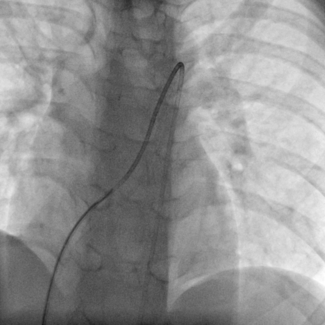

Masashi Yokoi, MD; Tsuyoshi Ito, MD; Junki Yamamoto, MD; Yoshihiro Seo, MD

A 79-year-old man with the diagnosis of acute myocardial infarction complicating cardiogenic shock received Impella CP (Abiomed) insertion via a femoral approach.